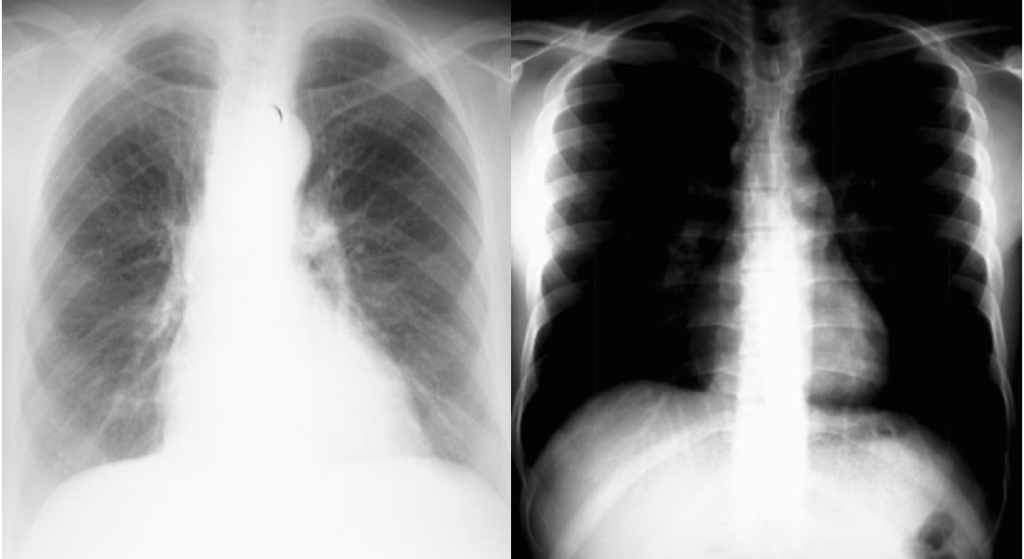

2. Determine Projection Type

- PA (Posteroanterior):

- Standard view, beam travels back → front

- Heart is near plate → minimal magnification

- Reliable for assessing cardiomegaly

- AP (Anteroposterior):

- Portable films or ICU patients

- Heart is further from plate → may appear artificially enlarged

- Supine:

- Patient lying flat

- Common in trauma/critical care

- Erect:

- Upright film (standing/sitting)

- Lateral:

- Side-on view for localisation or behind-heart lesions

- Mobile:

- Bedside; usually AP and supine